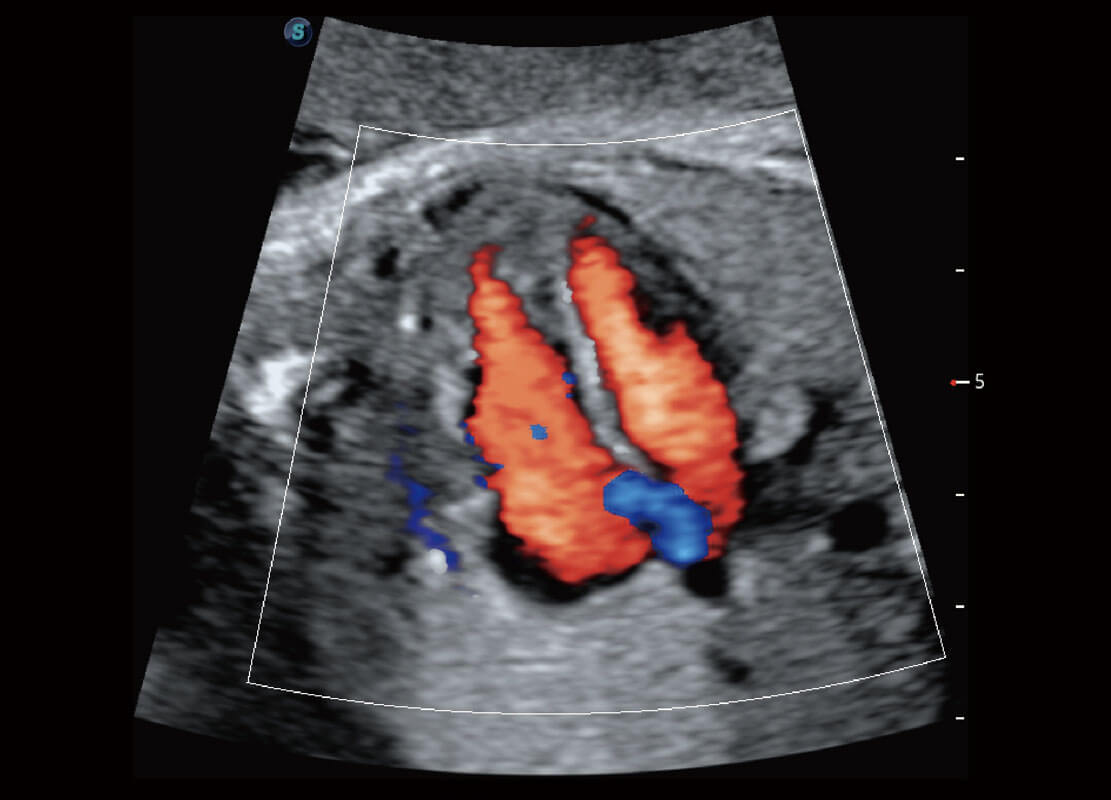

P60搭载一系列胎儿心脏成像技术,实现精细的胎儿心脏评估。

四腔切面

四腔心血流